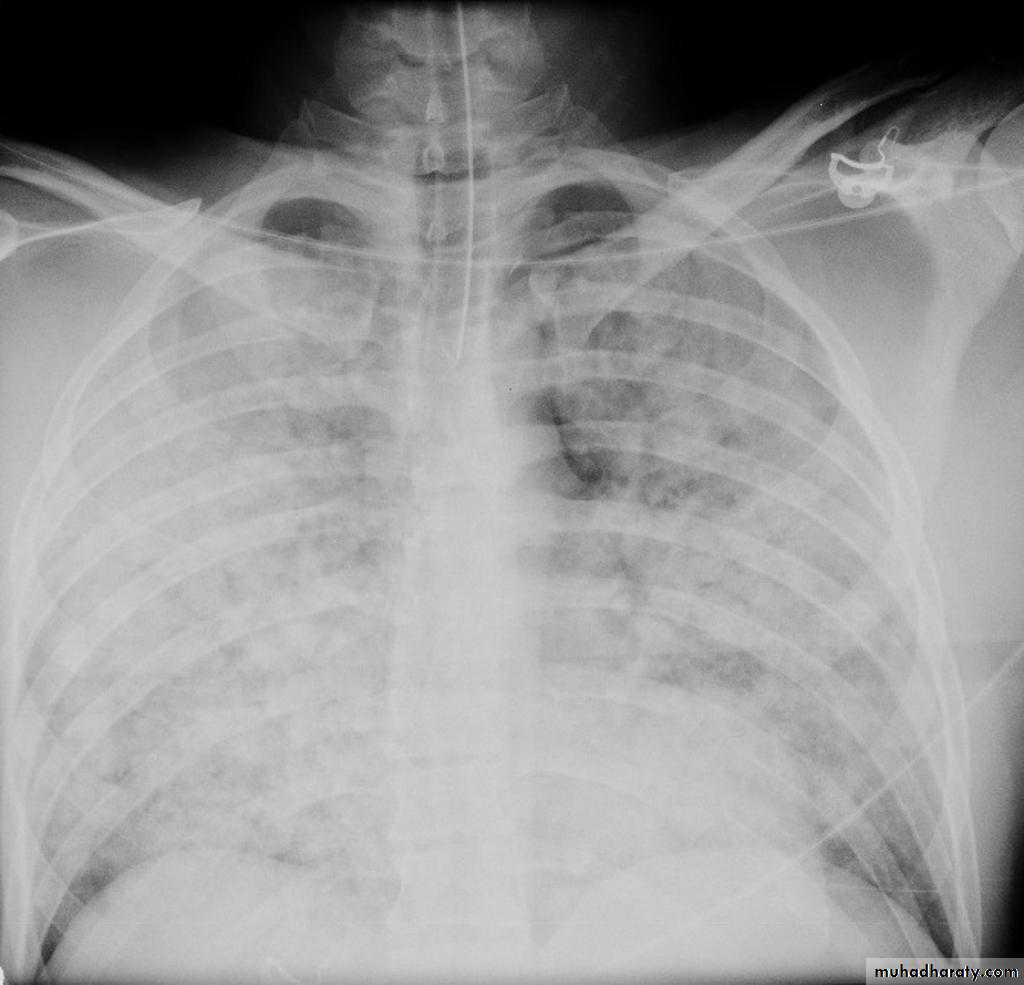

With left sided congestive cardiac failure, the features are that of pulmonary edema which includes:

central pulmonary venous congestion ( prominent hilum )

cephalisation of pulmonary veins ( upper lobe pulmonary venous diversion )

pulmonary interstitial oedema

pulmonary alveolar oedema

Cardiomegaly

Pleural effusion

Interstitial pulmonary edema

radiograph include if pressure > 25 mmHg the findings of :

cardiac size/cardio-thoracic ratio: useful for assessing for an underlying cardiogenic cause or associationbat wing pulmonary opacities

presence of peri-bronchial cuffing

septal lines: Kerley lines become more prominent

pleural effusions

pulmonary venous engorgement/pulmonary blood flow distributionupper lobe pulmonary venous diversion

Alveolar pulmonary edema